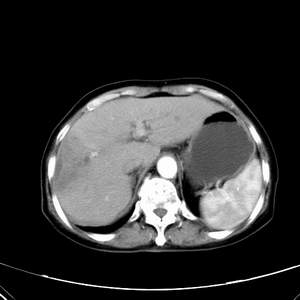

患者,女性,77岁,右上腹胀痛月余。afp正常。ca125升高。即往无肝炎病史。

肝右叶病灶是胆管细胞癌吗?门静脉右支癌栓形成?右侧肾上腺有问题吗?

快进快出符合肝癌表现

最后5幅图片是延时7分钟的。门静脉右前支内有充缺吗?如有,肝血管瘤不好解释。

病灶渐进性向心性强化,延时病灶中心见条片状高密度影,局部见肝包膜回缩征,结合病人无肝炎病史,考虑肝右叶胆管细胞癌,门脉右支癌栓形成。